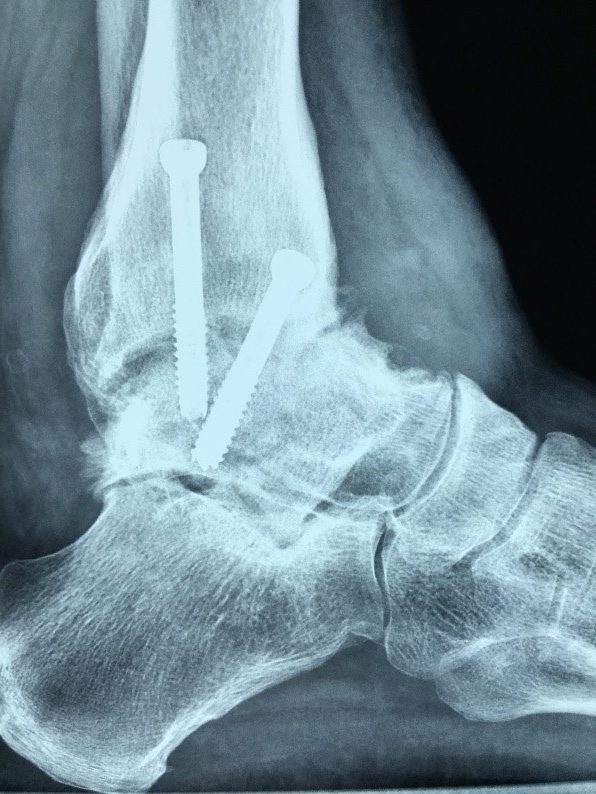

- L’Artrodesi della caviglia è un intervento abbandonato così come è stata abbandonata la artrodesi dell’anca e l’artrodesi del ginocchio.

Questa procedura chirurgica consisteva nel blocco della caviglia. Si praticava la fusione della tibia con l’astragalo. La caviglia si trasforma in un unico osso solido che non si muove più. Tipicamente, per stabilizzare la fusione si usano viti da sole o placche e viti. Dopo che la caviglia è bloccata il dolore può aumentare. I pazienti sono ad un rischio aumentato di sviluppare l’artrosi in altre articolazioni del piede dopo questa procedura. Si procede alla artrodesi della caviglia solo quando vi è una paralisi della gamba, nei casi di grande distruzione o di mancanza dell’osso oppure quando vi è una grave infezione dell’osso.